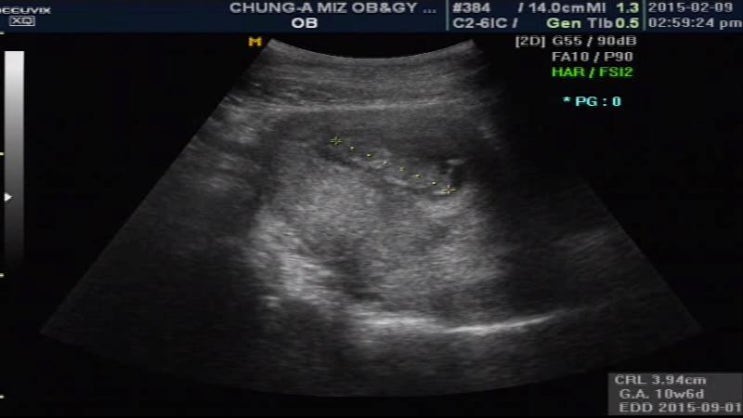

10주4일 - 제대로 안보여 ㅠㅠ

주말내내 몸이 넘 안조아서 누워잇고 병원갔다오고 ㅠㅠ 힘든 주말이였어요 그래도 어제 리언이를 만나는 ...